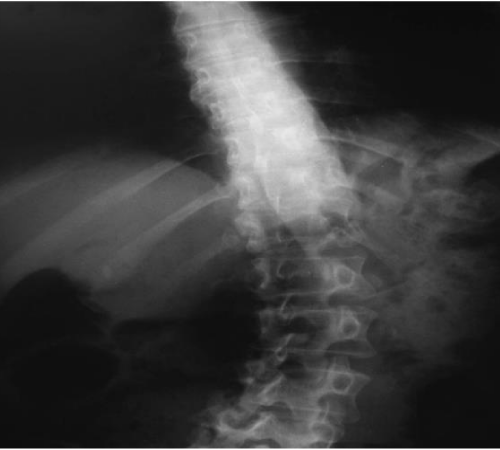

Diagnosis of PS requires at least 10° lateral flexion, which can be completely alleviated by passive mobilization or lying in a supine position [3,17]. Diagnosis of PS is based on the clinical evaluation of lateral displacement of the trunk, which is the first sign of postural misalignment usually reported by patients and their caregivers. Tracking can be done meticulously in day care clinical practice by goniometer, inclinometer or even by smartphone applications. X-rays in standing and supine positions is deemed necessary however standing is the most accurate method to assess the angle of curvature in the coronal and sagittal planes according to the Cobb angle to rule out other diagnoses [40,41] (Figures 2,3).

Figure 2: Anteroposterior radiograph of the PS patient exhibiting lean to the right.

Figure 3: Cobb’s angle.